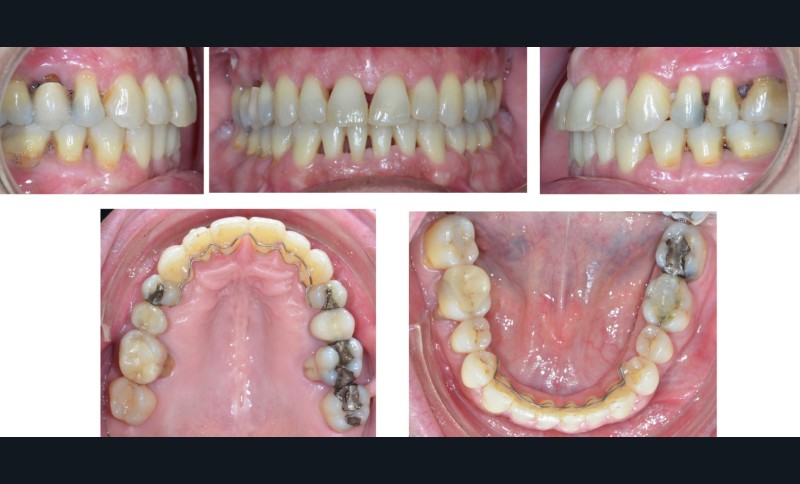

À l’examen endo-buccal (fig. 2), on note une formule dentaire complète (absence des 8) avec présence de restaurations multiples étanches, un bon contrôle de plaque et une parodontite de stade 4 grade C stabilisée [3], des récessions gingivales et des mobilités dentaires généralisées (degré 2, classification de Miller). L’arcade mandibulaire présente une courbe de spee importante avec égression du bloc incisivo-canin. Les milieux inter-incisifs sont alignés, le recouvrement est normal, le surplomb est augmenté à 3 mm et associé à des diastèmes et de la vestibulo-version des incisives maxillaires. Les relations antéro-postérieures canine et molaire sont en Classe I d’Angle.

L’analyse des moulages indique une dysharmonie dento-dentaire (indice de Bolton) par excès mandibulaire antérieur (0,7 mm).